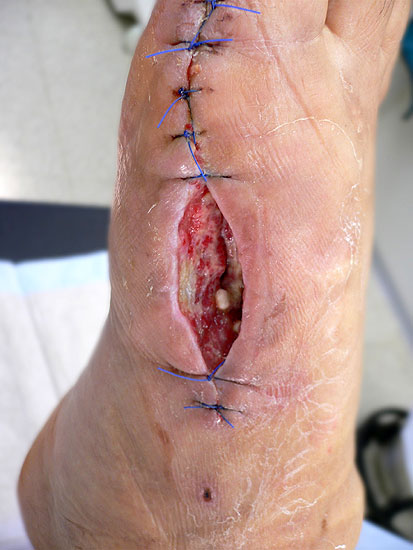

Wundheilungsstörung und Infekt

Zeichnet sich eine Wundheilungsstörung oder ein Infekt ab, hat sich unseren Händen ein aggressives Vorgehen bewährt. Die Antibiotika-Therapie erfolgt nach den allgemeinen Regeln für Knochen- und Weichteilinfekte. Lässt sich aufgrund der Weichteilschwellung nach operativer Revision ein primärer Wundverschluss nicht erreichen, kann durch eine mehrtägige Vakuumbehandlung der Wundgrund konditioniert werden 37. Nach Ausheilung des Infektes können Defektzonen bis ca. 4 cm durch eine Dermatotraktion sekundär verschlossen werden (Abb. 28). Hierzu werden Klammern in den Wundrand gesetzt durch welche ein elastischer Vessel-Loop eingezogen wird (Abbildung 29). Beim täglichen Verbandswechsel wird sukzessive die Vorspannung erhöht. Durch die gleichmäßige Traktion über mehrere Tage lässt sich so die Wunde verschließen. Bei mittelgroßen Defekten kann nach Konditionierung des Wundgrundes der Defekt mit Spalthaut verschlossen werden. Die großen Sehnenflächen am Fußrücken limitieren allerdings diese Technik 38. Auf freiliegen Sehnen gelingt es normalerweise nicht einen ausreichenden Granulationsrasen zu erzeugen, der die Basis für eine erfolgreiche Spalthauttransplantation bildet. In solchen Fällen, sowie bei größeren Defekten ist zeitnah die Mitbetreuung des Patienten durch einen plastischen Chirurgen sinnvoll 39. Mithilfe gefäßgestielter Lappen lassen sich auch großflächige Defekte kosmetisch zufriedenstellend verschließen (Abbildung 28).